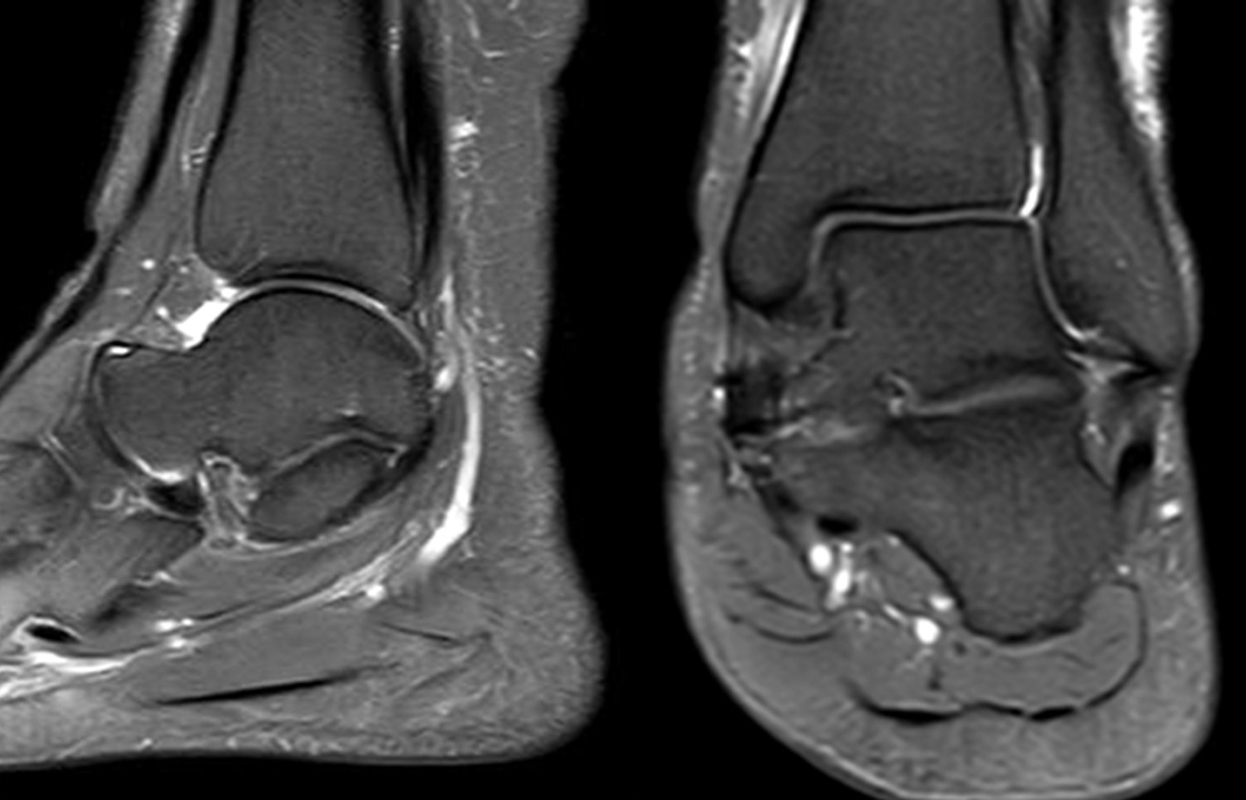

Abbildung 1.8.a und b: Akute Arthritis bei bekannter Gicht in beiden OSG: links die Früh-/Weichteilphase; rechts die Mineralisations­phase. Deutliche, entzündlich bedingte Mehranreicherungen in der Früh-/Weichteilphase. In der Mineralisation­sphase erkennt man die entzündliche Mitreaktion der subchondralen Gelenkabschnitte.

Abbildung 1.8.c - e: Akute Arthritis in beiden OSG, rechts > links. Im SPECT/CT erkennt man die Mitreaktion der subchondralen Gelenkabschnitte. Die Arthritis ist so akut, dass (noch) keine ossären morphologischen Veränderungen im CT abgrenzbar sind.